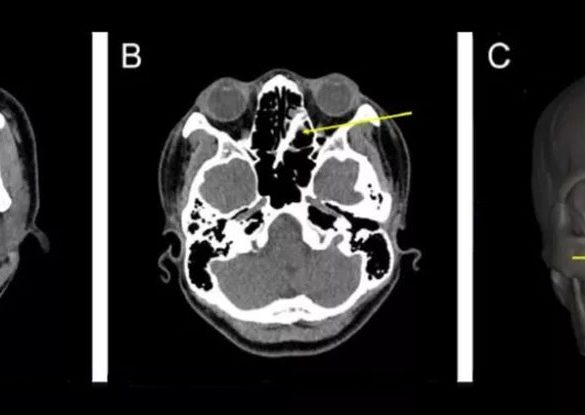

A teen who had experienced years of nasal congestion along with a mysterious “foul odor” when he blew his nose...

A woman in Taiwan unknowingly had two chopstick fragments lodged in her sinuses for a week after a violent fight...